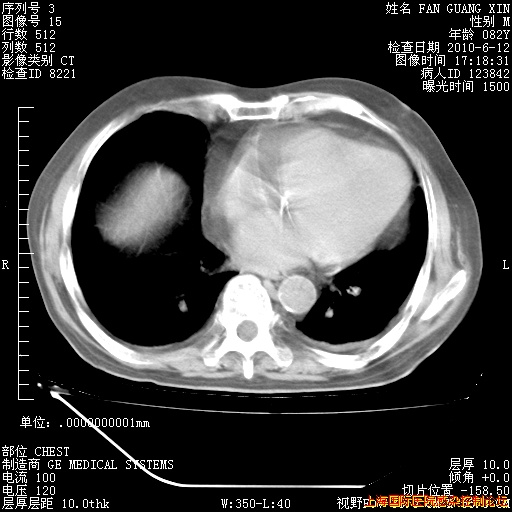

补发6月12日肺部CT肺窗

6月12日肺窗